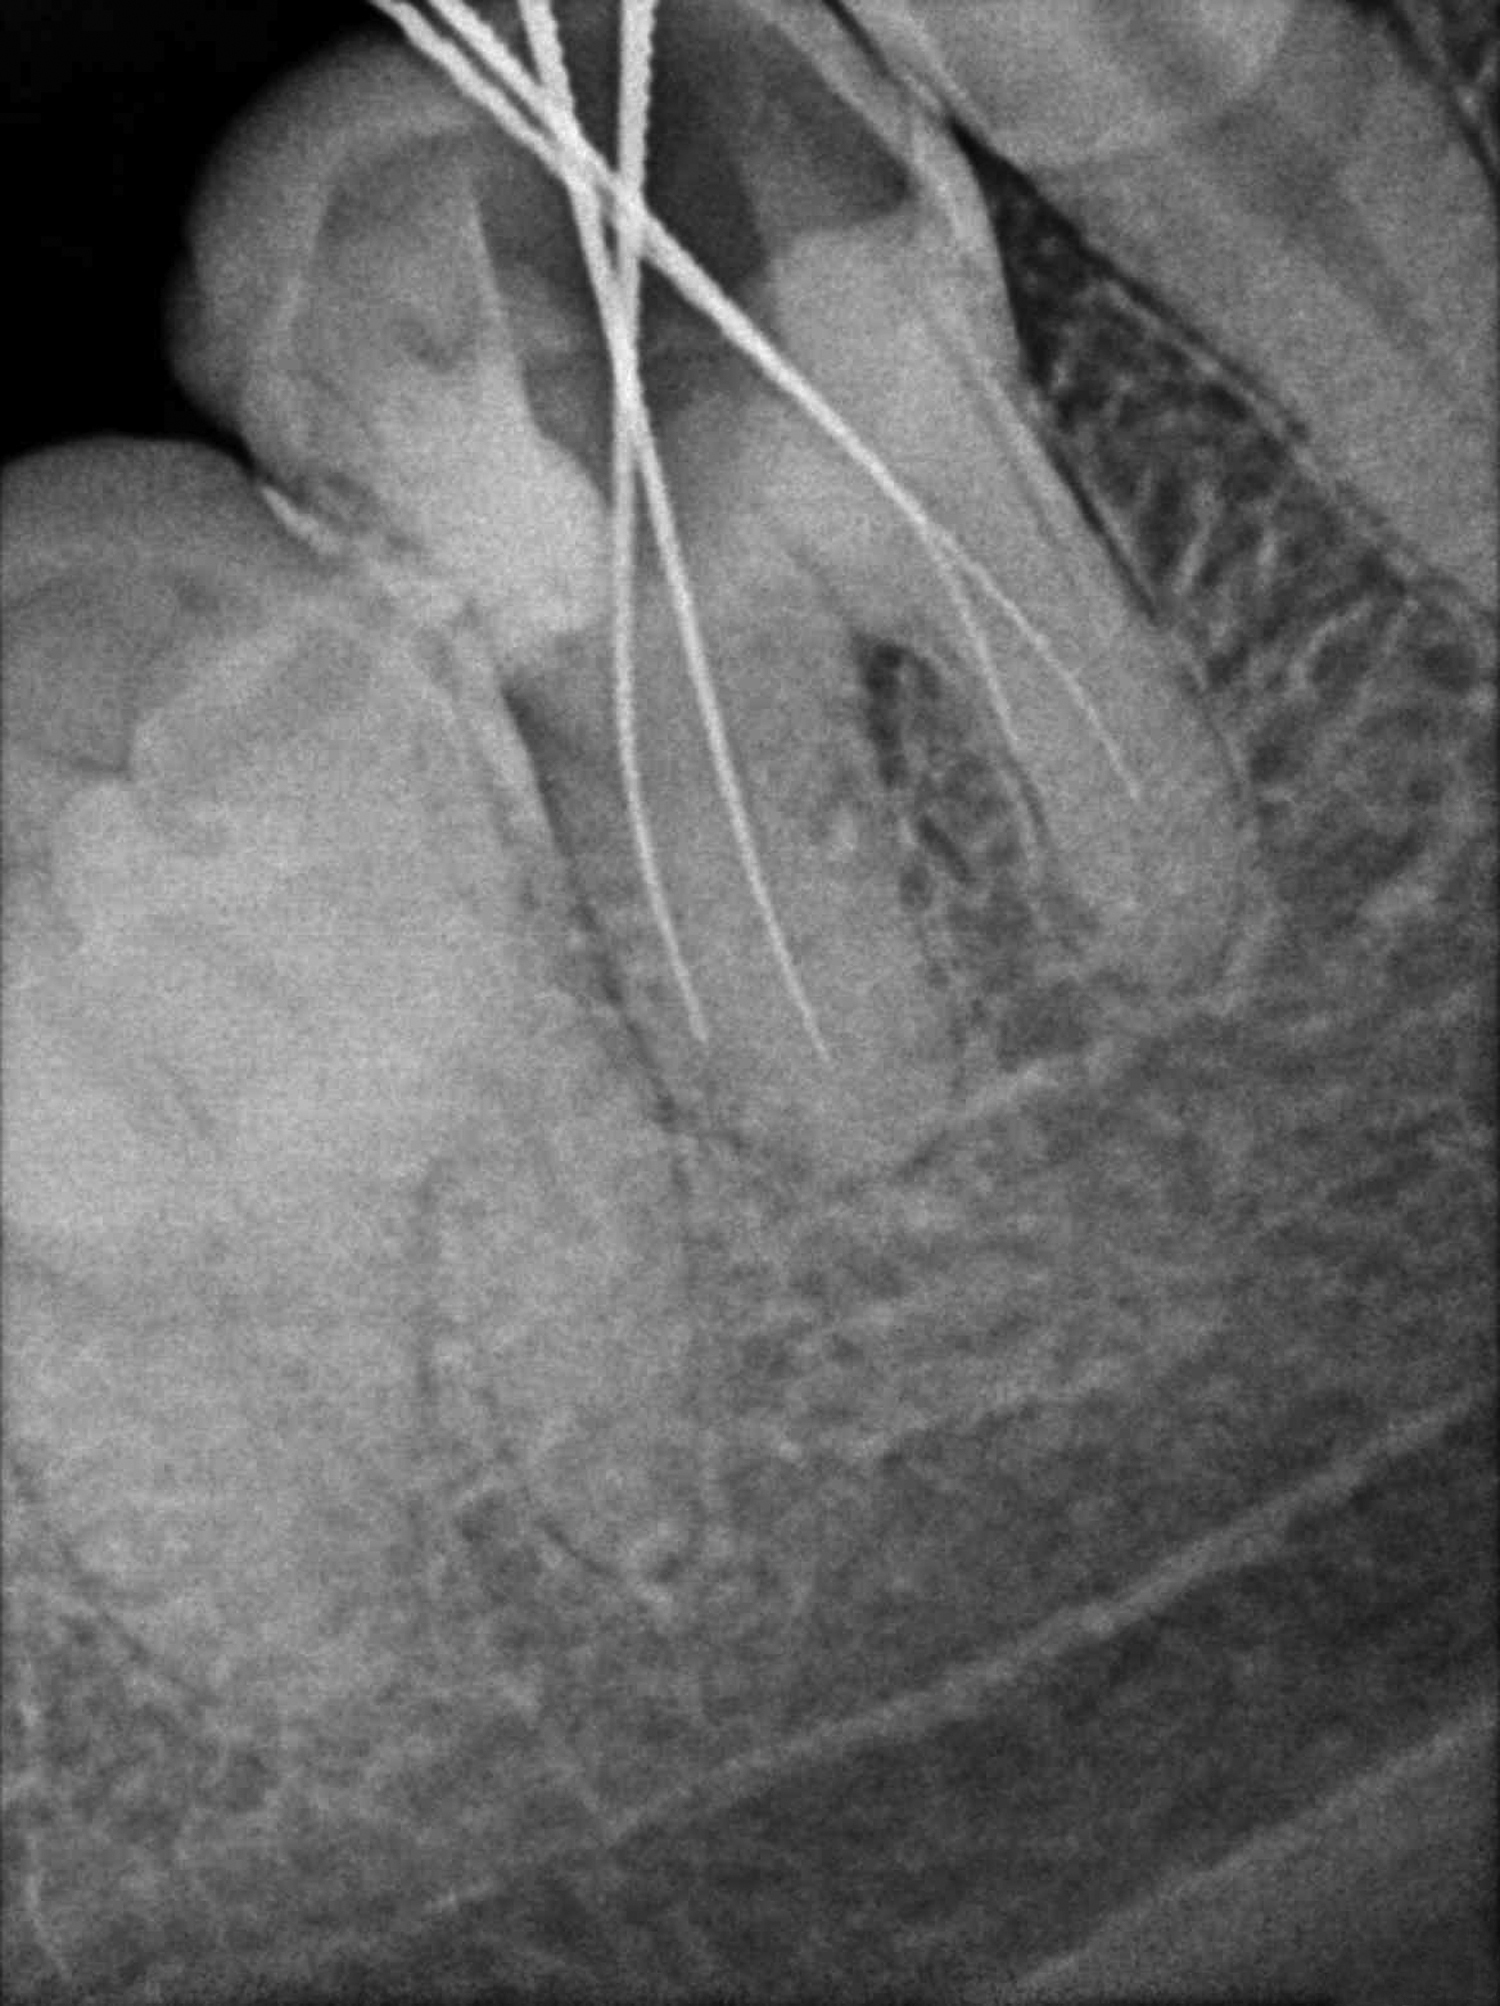

A 34-year-old male patient presented to the Department of Conservative Dentistry and Endodontics with a complaint of persistent low grade pain in right mandibular first molar since a fortnight. There was no contributory medical history or history of other dental treatment. Intraoral examination revealed caries with 45 and 46. No other teeth in the oral cavity were cariously involved, 46 showed deep mesio-occlusal caries involving the pulp and was sensitive to vertical percussion with no mobility or periodontal involvement. Vitality testing with the electric pulp tester gave a delayed response indicating irreversible pulpitis. Root canal treatment was initiated and after pulp extirpation, a rough working length estimation X-ray was taken. On this radiographic examination, an incomplete vertical fracture line involving the furcation area was noted [Table/Fig-1]. The bone support of both roots was good and not periodontally compromised in any manner. There was no periodontal or furcation involvement seen in relation to 46. A disto-occlusal composite resin restoration was planned for 45. An assessment of all findings was made and a treatment protocol was developed to achieve functional preservation of the tooth in the arch.

Diagnostic radiograph of 46 showing incomplete vertical fracture in the furcation area.

In the treated case, the fracture line, observed in the initial radiograph [Table/Fig-1], extended from the furcation area towards the point of bifurcation at the floor of the pulp chamber. During access cavity preparation, it was observed that the fracture line did not extend into the pulp chamber; thus, confirming the diagnosis of incomplete vertical furcation fracture. Vertical furcation fracture is a vertical crack that extends vertically from the floor of the pulp chamber in a mandibular molar towards the furcation area of the roots. The pulp is mostly involved in a vertical furcation crack and the tooth is vaguely symptomatic until the fracture line propagates and mobility sets in. The tooth rarely separates into two pieces because the tooth is held in position by the surrounding bone. The prognosis for this type of crack is fair but it depends on how deep the crack extends into the internal aspect of the tooth. The options are to treat the tooth with a root canal followed by a build up, post and crown or to extract the tooth [3]. Several classifications have been proposed to better explain vertical tooth fractures [4,5] (by Leubke and others), but there is scant mention in literature of vertical fractures restricted to the furcation area with incomplete progression of the fracture line.